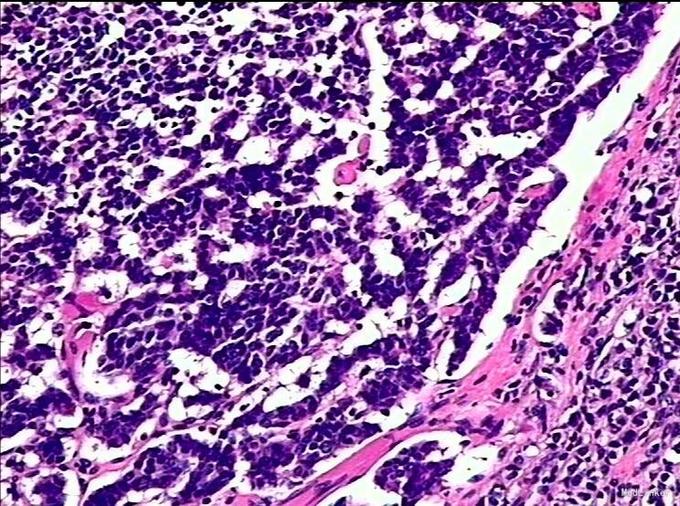

查体:无特殊。 辅查:外院PET/CT:纵隔肿瘤,胸腺癌可能。术后病理示:(胸壁肿物、纵膈结节、前胸壁肿物)非典型类癌。(胸腺上极)增生的纤维、脂肪和血肿,未见肿瘤。(左侧胸壁肿物)增生的纤维、脂肪组织内可见散在萎缩的胸腺,未见肿瘤。(左侧胸壁肿物)主要为纤维、脂肪组织伴出血明显。

诊断:胸腺非典型类癌 治疗:患者入院后完善各项检查,未见手术禁忌症,做好术前准备后行正中开胸胸腺扩大切除术+上腔静脉重建术,术后恢复良好。

胸腺神经内分泌细胞肿瘤分为两大类,一类是胸腺类癌,另一类是胸腺小细胞癌。1/3~1/2 的患者在手术确诊前无症状,于胸部 X 线检查中无意发现。而少数患者仅有前胸疼痛、咳嗽、咯血、气促等非特异性症状。